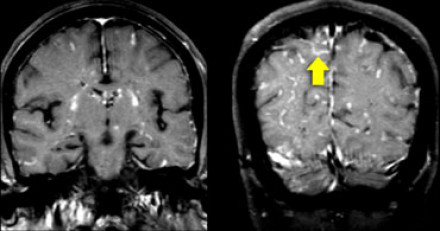

圖片二

在上圖中,是各種多發(fā)性增強白質(zhì)病灶圖像,我們對其中部分病例進行詳細討論。需要說明的是,以下鑒別診斷中提到的疾病與上圖中的圖像并不完全重合。

血管炎

大多數(shù)血管炎性疾病的MRI成像特點是點狀增強。

腦部血管炎常見于系統(tǒng)性紅斑狼瘡、結(jié)節(jié)性多動脈炎(PAN)、白塞病(Behcet)、梅毒、韋格納肉芽腫(Wegener)、干燥綜合征(Sjogren)和原發(fā)性中樞神經(jīng)系統(tǒng)血管炎。

白塞病(Behcet)

白塞病更常見于土耳其患者。典型MRI表現(xiàn)是急性期出現(xiàn)腦干病灶結(jié)節(jié)性增強。

其他疾病的腦轉(zhuǎn)移病灶

其他疾病的腦轉(zhuǎn)移病灶周圍常包裹有水腫帶。

交界區(qū)腦梗死

周圍交界區(qū)腦梗死在病變早期可出現(xiàn)增強病灶。